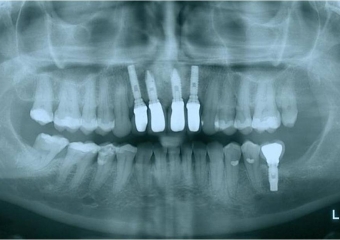

Raio X final